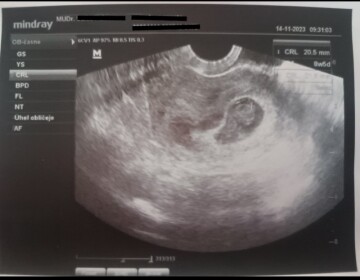

Dobrý den přeji. Jsem 6+6 tt dle menstruace. Dnes jsem byla na kontrolním ultrazvuku u svého gynekologa. Ten však neviděl bijící srdíčko. Chtěl se ujistit a tak mě poslal na sono do nemocnice. Tam paní doktorka též řekla, že srdíčko nevidí. Teď mám týden počkat a poté dojít na další kontrolu. Vím, že nejste vědma, ale chci se spíš zeptat, zda je možné, že by srdíčko ještě během těchto dní začalo bít? Že by ještě srdeční akce nemusela bit třeba i viditelná. Děkuji za odpověď.

Dobrý den,

datace dle menstruace nemusí být zcela přesná, k oplodnění mohlo dojít v pozdější fázi menstruačního cyklu a může se stát, že těhotenství je ve fázi, kdy ještě zcela bezpečně srdeční akce nemusí být vidět. Určitě je nutné vyčkat kontrolního ultrazvuku s odstupem.